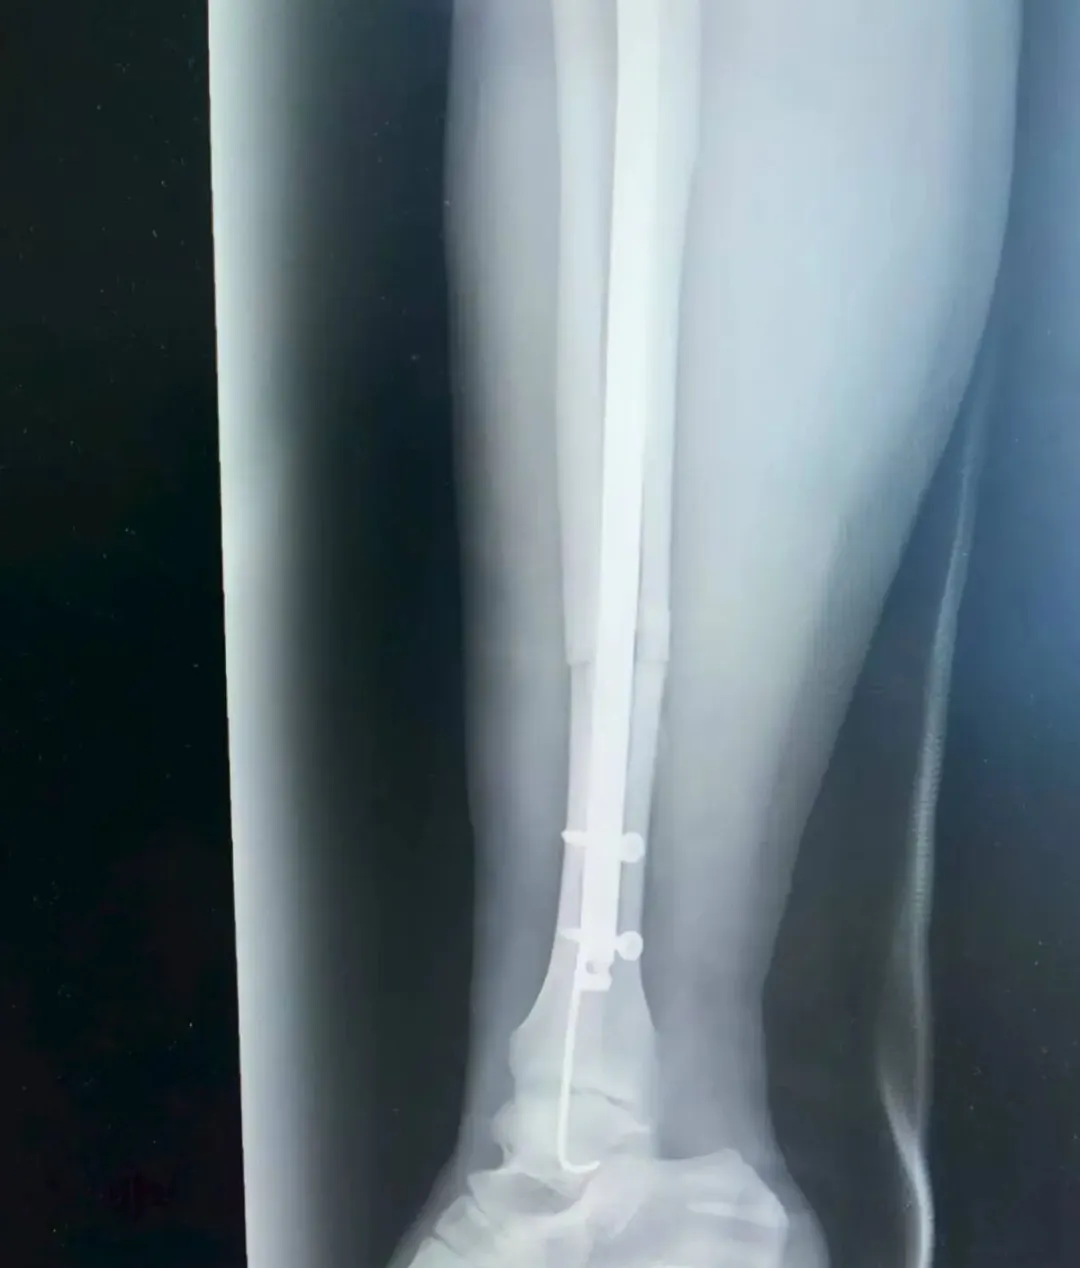

经过诊断,张女士为右侧胫腓骨闭合性骨折,且骨折端移位明显,同时伴有严重软组织肿胀,手足外科孙毅珲主治医师第一时间通过药物与物理治疗控制肿胀、石膏外固定等避免继发性损伤,为后续手术创造安全条件。

考虑到张女士是外地游客,不仅希望骨折能精准复位,还盼着创伤小、恢复快,不耽误后续返程与康复。董伟副主任医师结合影像学资料,综合考虑张女士的身体状况与个人需求,最终确定采用“胫腓骨骨折闭合复位+胫骨髓内钉内固定术+腓骨髓内针内固定术”,全程无需做大切口,通过微创方式实现骨折端精准对位,既能最大程度保护肿胀的软组织,又能显著提升术后恢复速度。

手术由董伟、孙毅珲共同完成,术中借助C臂机实时透视引导,小心翼翼地通过闭合复位技术调整骨折端位置,确保达到解剖复位标准;随后精准植入胫骨髓内钉与腓骨髓内针,完成固定。整个手术过程出血少,术后仅留下几个微小创口,最大程度减少了张女士的痛苦。